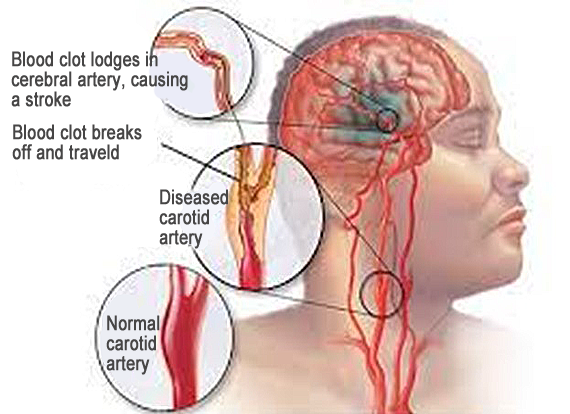

– A stroke

– Cerebral infarction and Cerebral hemorrhage